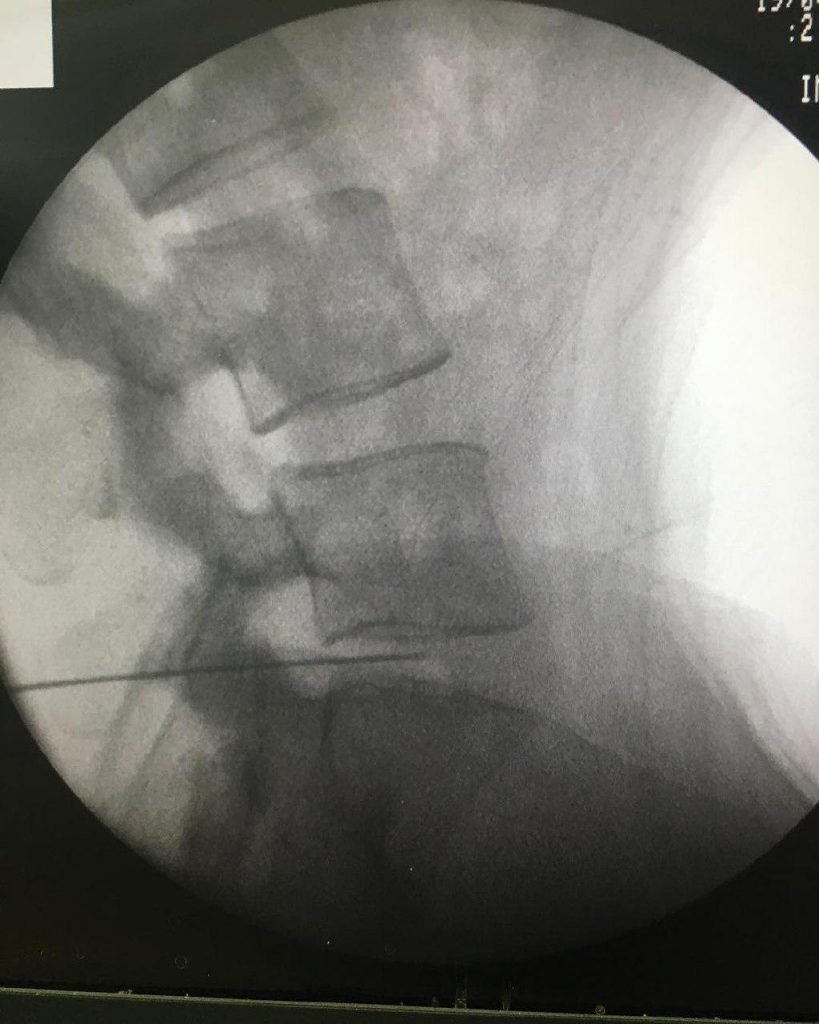

-لیزر(جراحی بسته) دیسک کمری

-اوزون تراپی دیسک بین مهره ای

-درمان تنگی کانال نخاعی غیرقابل جراحی

استفاده از روشهایی مانند تزریقات تخصصی (مانند اپیدورال، بلوک عصبی)، طب سوزنی، فیزیوتراپی، تحریک الکتریکی عصب و روشهای کم تهاجمی جراحی.